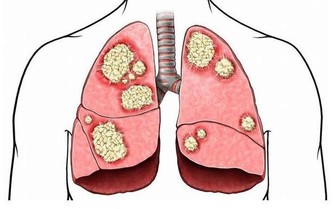

(4)皮膚暗紫:重度肺氣腫

由於缺氧,血液氧合血紅蛋白含量升高。

當還原血紅蛋白升高到每100毫升血液5克以上時,血液就會變成暗紫色。此時病人的皮膚、黏膜出現紫紺;皮膚出現暗紫的情況常見於重度肺氣腫、肺源性心髒病、發紺型先天性心髒病等。